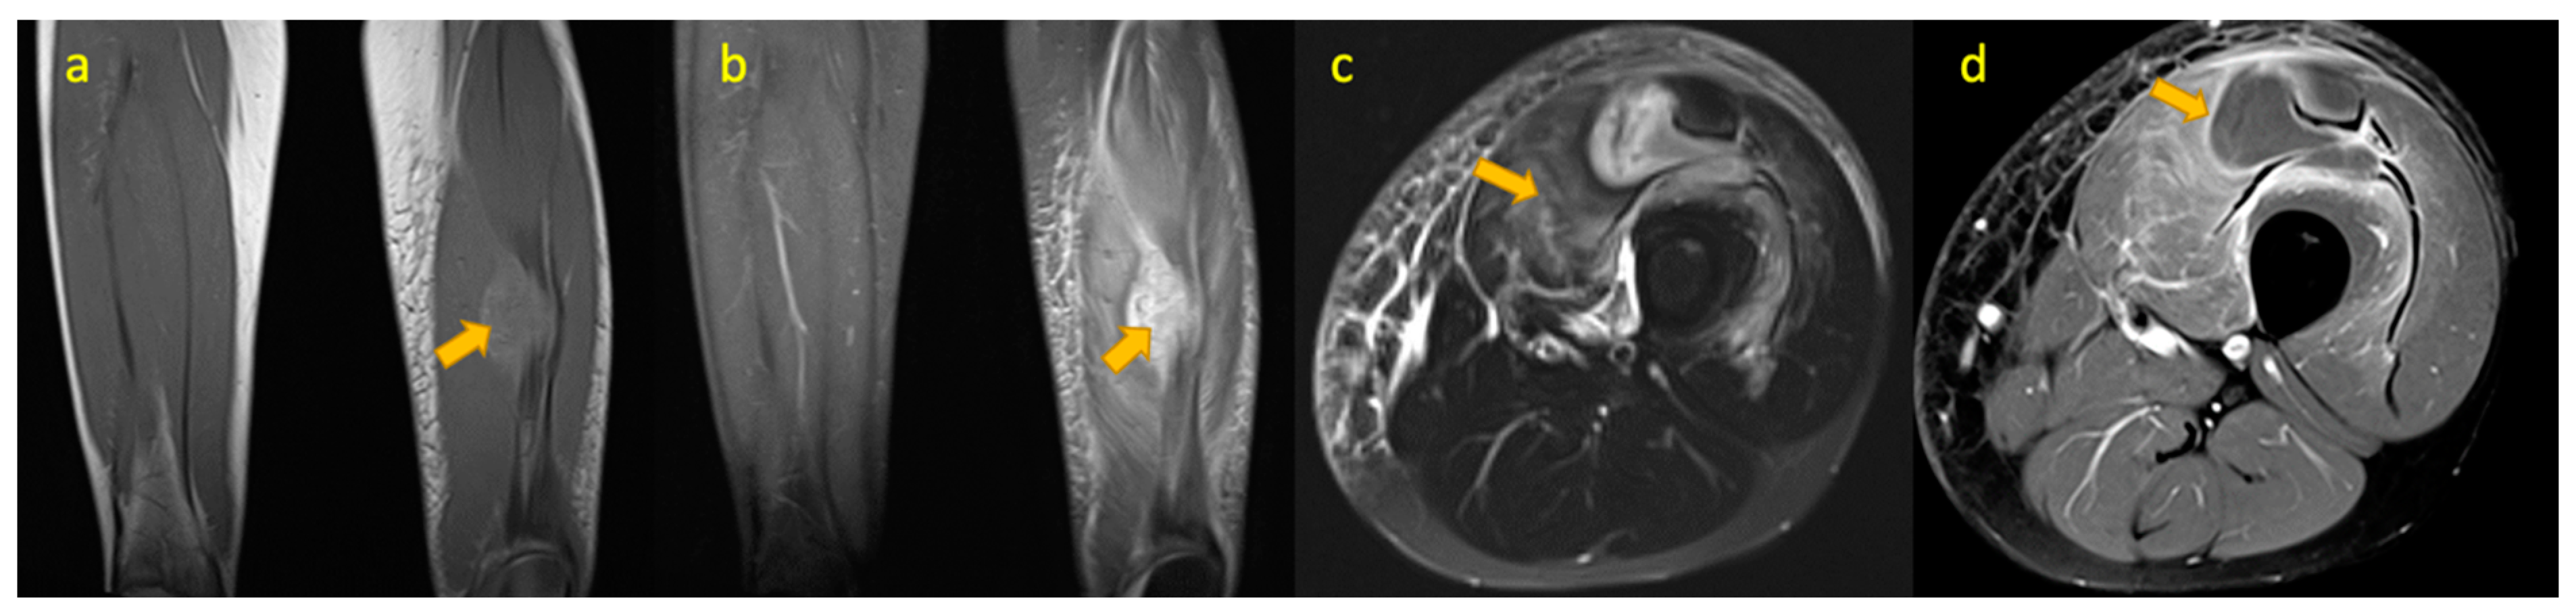

15. TB(Tuberculous) Pyomyositis Thigh